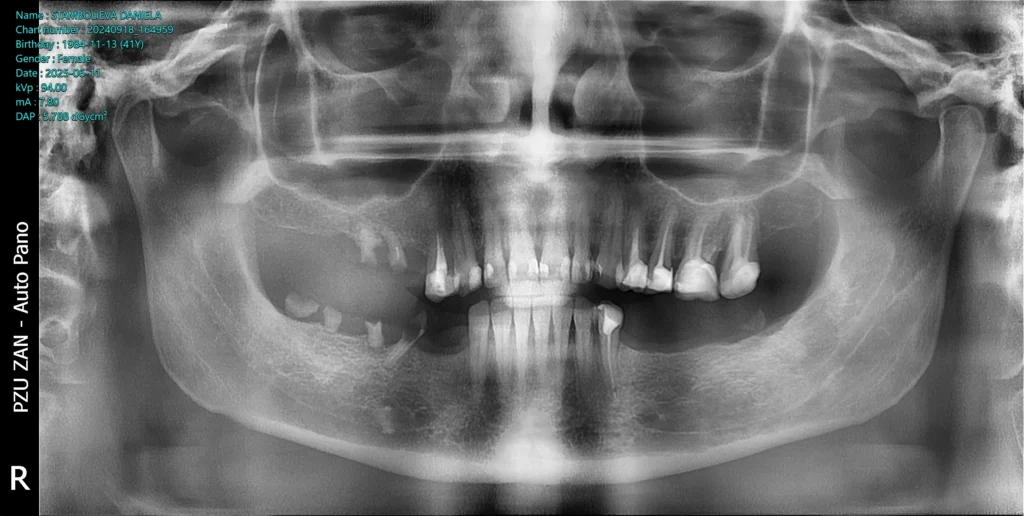

This patient came to our clinic from Bulgaria. She had a severe fear of dentists, multiple lost teeth in both jaws and an uneven bite because of that.

After the examination and the analysis, the therapy plan was full mouth reconstruction with dental implants and zirconia crowns and bridges. The remaining roots were extracted and six dental implants were placed using a surgical guide and digital workflow.